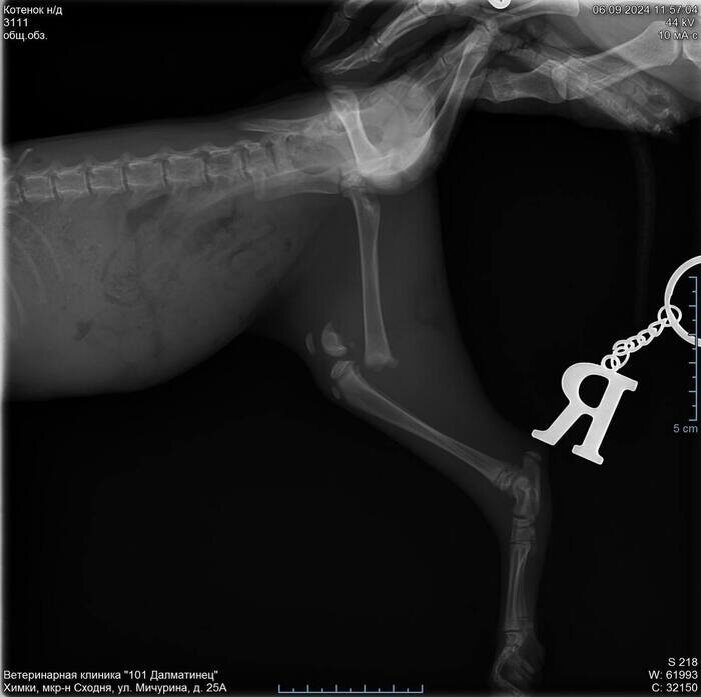

У Ириски имеется одна особенность - в следствие наезда автомобиля и перелома ноги у нее не работает ниже бедра задняя правая лапа, так же отсутствует чувствительность. Найдена с переломанной лапой она была на парковке возле ТЦ где работает девушка, по камерам было видно, что Ириску выбросили из авто, а буквально в следующий момент её сбила сзади идущая машина.

Вот в каком виде её нашли:

Далее у коти была операция с установкой спиц и последующем их извлечением, деньги на операцию собрали сотрудники ТЦ за пару часов.